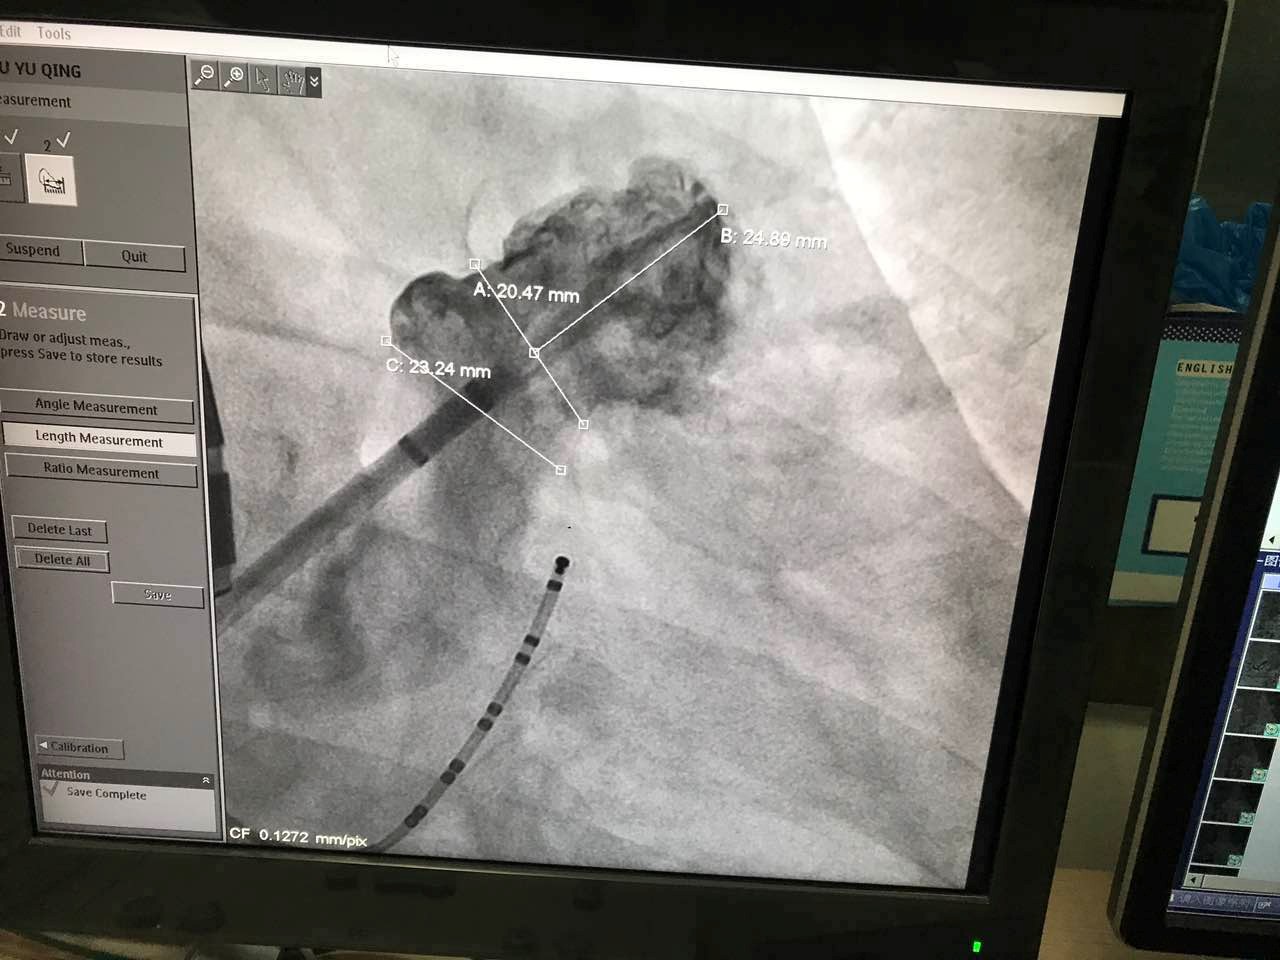

7月3日11点10分,第二例使用LAmbre™左心耳封堵器进行的封堵手术顺利进行。该患者为61岁男性,术中测量患者左心耳开口为21mm,左心耳深度为25mm。本例手术选用型号为2632的LAmbre™左心耳封堵器。黄鹤主任和林逸贤医生诊疗团队精湛的医术配合以LAmbre™左心耳封堵器杰出的设计和卓越的术中性能,不到半小时便完成对病人左心耳的完全封堵。本例手术的主要术者之一,在国际上拥有多年左心耳封堵手术经验的林逸贤医生于术后表示:“相较于其它同类产品,LAmbre™左心耳封堵器极大的简化了手术过程,缩短了手术时间。”

图:术中造影